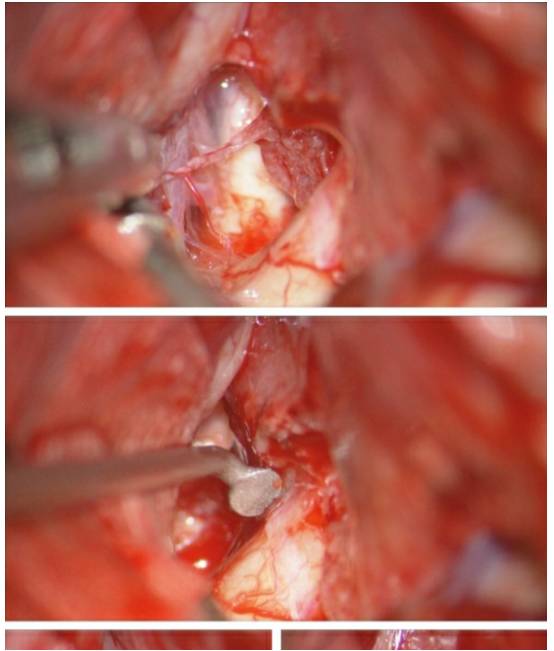

图17. 该蝶骨嵴内侧脑膜瘤的纤维样包膜很难松动,最后将肿瘤沿着ICA的长轴分为两半,才得以切除。首先在颅底识别颈动脉近端和视神经(上图)。然后将肿瘤沿着ICA的长轴切开(下图),这样有利于松动肿瘤,并最终将肿瘤的前后两部分切除。

图19. 图示为位于右侧视神经孔的第三组脑膜瘤(上图)。硬膜外床突切开,打开视神经的顶面(中图),为硬膜内打开镰状韧带、切除视神经管内肿瘤做准备。打开硬脑膜,抬起额叶,即可在神经内侧面看到向视神经管外延伸的肿瘤部分(下图)。

图20. 用Karlin刀片(Symmetric Surgical,Antioch,TN)切开肿瘤表面靠近术者一侧的镰状韧带(上图)。用锐性分离技术将肿瘤位于视神经管外的部分从神经表面解剖出来,并用垂体咬钳将肿瘤剥除。

图21. 保留供应视交叉的小穿支血管(上图),用带角度的剥离子将术野盲区中围绕视神经内侧的管内肿瘤部分分离出来(中图)。用带角度的直剥离子探查视神经管远端,以确保充分的减压,也可以用显微手术镜来加以确认(下图)。